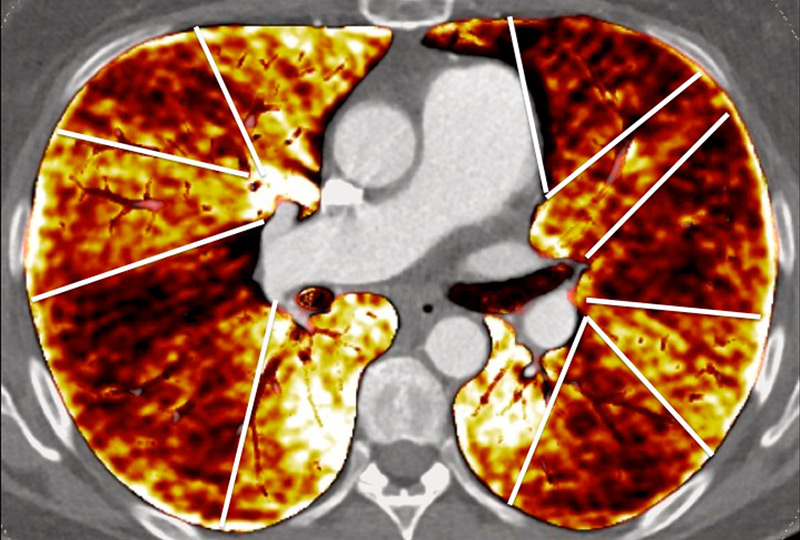

Nowadays, DECT imaging can be used for pathologies other than CTEPH and seems to offer advantages for PH characterisation because different DECT findings have been described in acute pulmonary embolism, CTEPH and idiopathic PAH (IPAH). In fact, perfusion defects are smaller and less defined in PAH than in CTEPH. This is likely due to focal under- and overperfusion as a result of the structural pulmonary vascular changes that occur in PH, which include vascular endothelial damage, cellular proliferation and occlusion in the distal pulmonary vasculature. Perfusion heterogeneities in DECT imaging are also common and seen in most cases of PAH. Findings of perfusion inhomogeneities related PAH have long been recognised in scintigraphy, and often are referred to as having a “mottled” pattern [42]. These perfusion defects are different from those seen in CTEPH, with nonsegmental and poorly defined defects (fig. 5). This heterogeneity is related to the severity of the disease. In PAH, this perfusion variability on scintigraphy is well correlated with pulmonary vascular resistance, as Talwar et al. showed [43]. Recently, similar results were published for DECT techniques (fig. 6). Ameli-Renani et al. described an increased enhancement of pulmonary arteries with reduced iodine lung perfusion in PH, and a good correlation of DECT perfusion heterogeneities with pulmonary vascular resistance; they showed a greater heterogeneity in parenchymal iodine maps in PH without pulmonary embolism [13]. The authors concluded that perfusion heterogeneities seen in DECT appear to be a direct reflection of pulmonary vascular resistance.

Figure 6

Perfusion heterogeneities in idiopathic pulmonary artery hypertension (stars) in two different patients (A/B). The dilatation of the arteries in pulmonary hypertension (arrows) is not always observed depending on the severity of pulmonary hypertension.